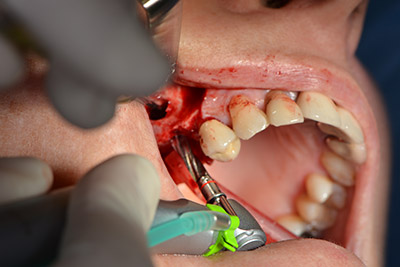

Danach wird das Implantat eingebracht und der Knochen aufgebaut. Aufgrund der Größe des Augmentates wurde im vorliegenden Fall Eigenknochen, der als Bohrspäne bei der Implantation 16 und der Fenestration 14 angefallen ist und mit einer Knochenfalle aufgefangen wurde, mit Knochenersatzmaterial vermischt.

Eine resorbierbare Membran bildet die Barriere nach bukkal und deckt das Augmentat ab. Zum Schluss wird speicheldicht vernäht. (Abb. 15 bis 19).